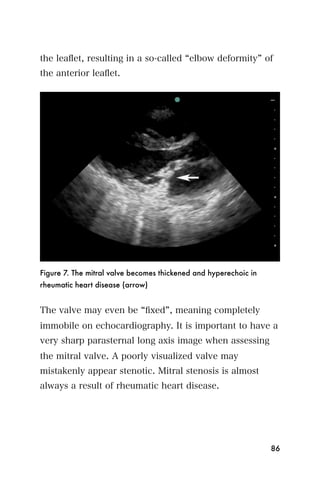

Figure 7), and the valve does not open well. Typically,

the leaflet, resulting in a so-called elbow deformity of

the anterior leaflet.

Figure 7. The mitral valve becomes thickened and hyperechoic in

rheumatic heart disease (arrow)

The valve may even be fixed , meaning completely

immobile on echocardiography. It is important to have a

very sharp parasternal long axis image when assessing

the mitral valve. A poorly visualized valve may

mistakenly appear stenotic. Mitral stenosis is almost

always a result of rheumatic heart disease.